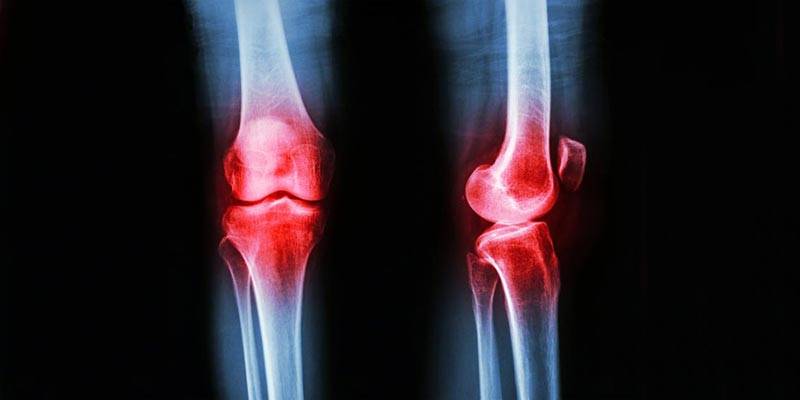

Células tronco para tratar artrose de joelho

A artrose de joelho vai afetar 2/3 da população mundial e a chance aumenta quando se pratica corrida, basquete, vôlei.  Esse desgaste acontece porque a camada protetora do joelho chamada cartilagem vai gastando ao longo da vida.

Quando se fala em medicina esportiva e desgaste de cartilagem você vai precisar realmente de alguém especializado. Os novos tratamentos para desgaste de cartilagem tem mostrado resultados impressionantes, com a estatística mundial falando em 70% de bons resultados. Estes novos tratamentos não são uma substituição, mas sim uma adição aos tratamentos que já existem. Podemos falar em três tratamentos basicamente: